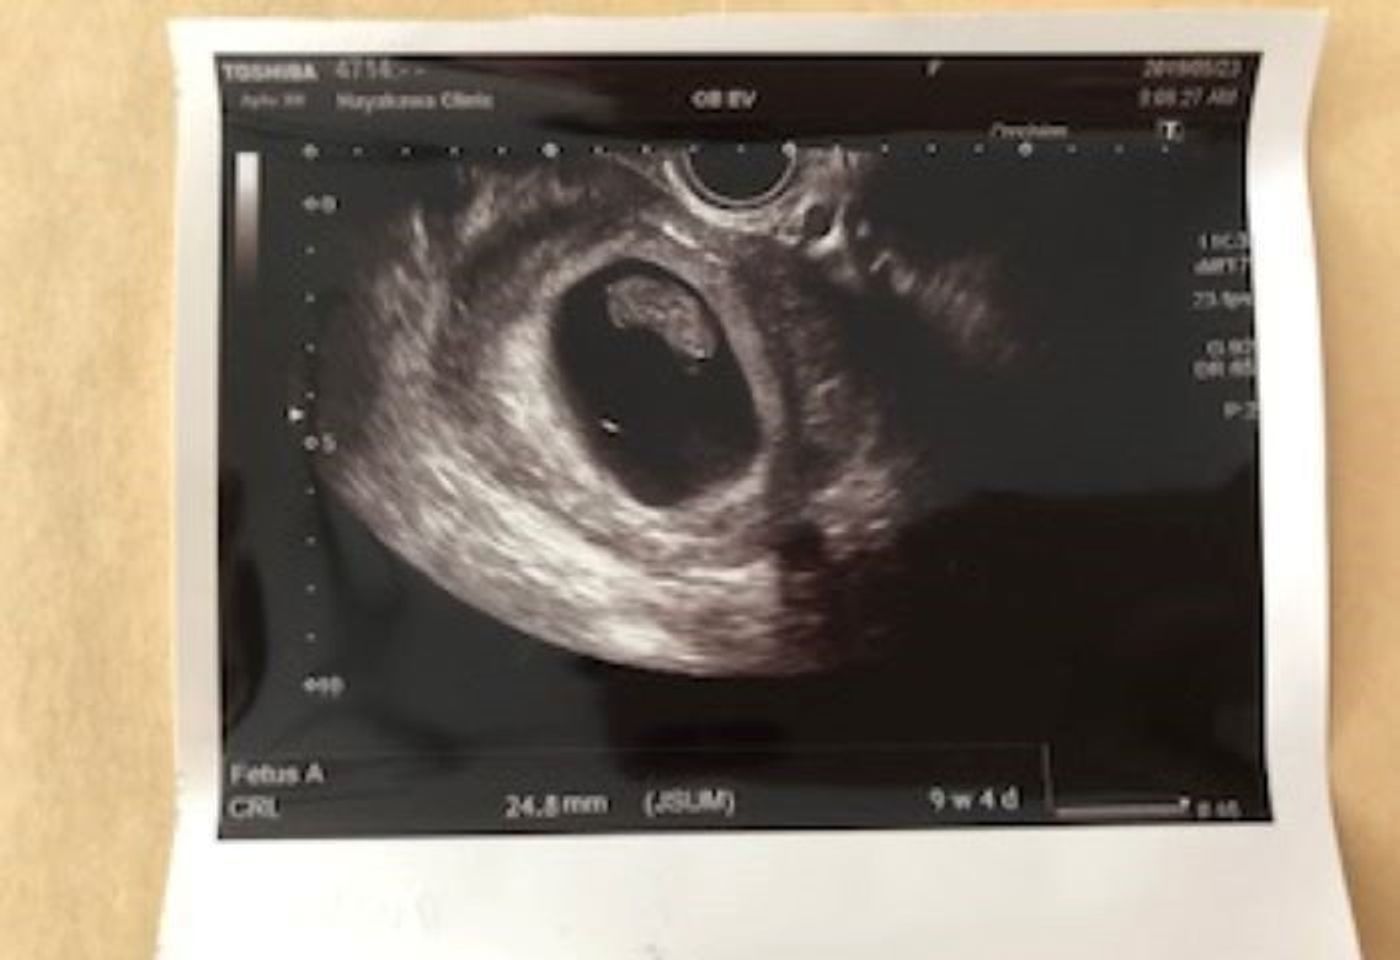

稽留流産 手術前 エコー

稽留流産に至った場合、自然に体外に排出されるのを待つか手術を行うかをその後の経過を観察して決めることになります。 化学的流産とは? 妊娠が判明した後は妊娠健診でエコー検査を受ける流れとなりますが、 エコー検査の前に流産が起こってしまう 稽留流産の診断 エコーで2頭身の姿が見えて、可愛いなと思ったんですが、今まで見えてた心拍の点滅がないことにすぐに気が付きました。 まったく動かない赤ちゃん。 女医さんが焦ったように何回か位置を変えてエコーしてくれましたが、心拍は確認 この春、人生で4回目の妊娠をしました。 双子かも?!と言われてからの稽留流産診断。激動の2ヶ月でした。 妊娠発覚→流産診断→自然排出までの症状やエコー写真とともに記録したいと思います。 3月10日 生理開始 いつも通りの